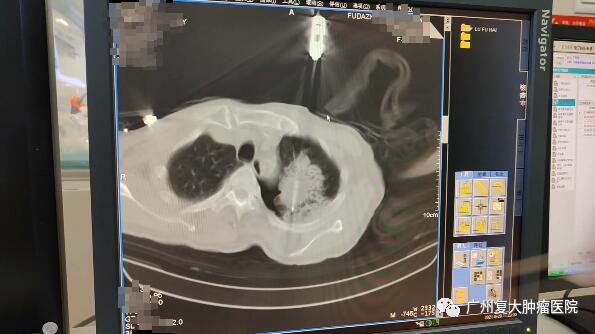

因此,牛立志院长合理利用人工气胸这一辅助手段,提供消融的安全性与有效性。随后,在CT引导下,以左下肺肿瘤(大小约3.3cm×3.0cm×2.9cm)为穿刺靶区,用穿刺活检枪穿刺左上肺肿瘤,CT扫描穿刺到位后取出肿瘤组织4条送病理检查;再用超冷刀经穿刺点穿刺到肿瘤靶区,CT扫描到位后快速冷冻至-130℃~-150℃,待冰球覆盖靶区,复温后拔除超冷刀,包扎穿刺点,完成消融。

进行冷冻消融